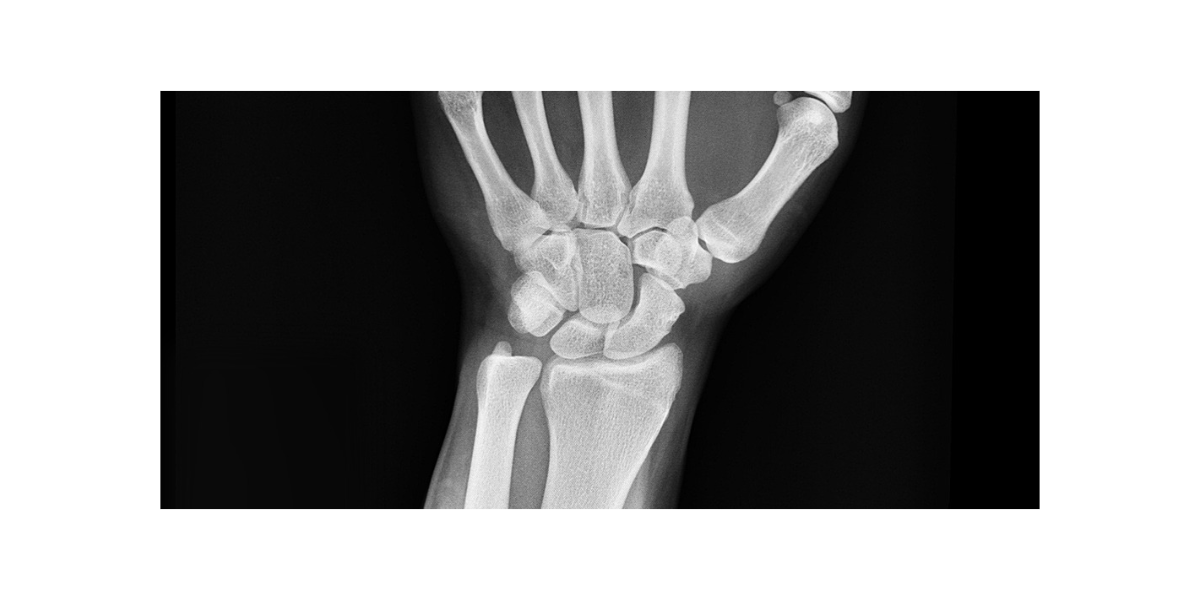

손목터널증후군은 손목에 있는 작은 통로인 '수근관' 안을 지나는 정중신경이 압박을 받아 발생하는 질환입니다. 이 정중신경은 손의 감각과 운동을 담당하는 중요한 신경인데, 반복적인 손 사용이나 손목의 과도한 굴곡, 염증 등으로 인해 수근관 내부 압력이 증가하면 신경이 눌리면서 증상이 나타납니다. 가장 일반적인 원인은 반복적인 손목 사용입니다. 컴퓨터 키보드 작업, 스마트폰 사용, 손으로 무거운 물건을 자주 드는 행동 등이 손목에 지속적인 부담을 줘 수근관 내부를 좁게 만듭니다. 또한 임신, 당뇨병, 류머티즘관절염, 갑상선 질환 등도 손목터널증후군의 위험 요인이 될 수 있습니다. 특히 임산부는 호르몬 변화로 인한 부종 때문에 신경 압박이 발생하기 쉽습니다. 선천적으로 수근관이 좁은 사람들도 이 질환에 걸릴 가능성이 높습니다. 또한 나이가 들면서 손목 주변 인대와 조직이 퇴행성 변화로 인해 두꺼워지거나 굳어져 정중신경을 자극할 수 있습니다. 즉, 단순한 피로나 근육통으로 생각하고 넘기기 쉬운 손목 불편함이 반복된다면 반드시 원인을 파악하고 조기에 대처해야 합니다.